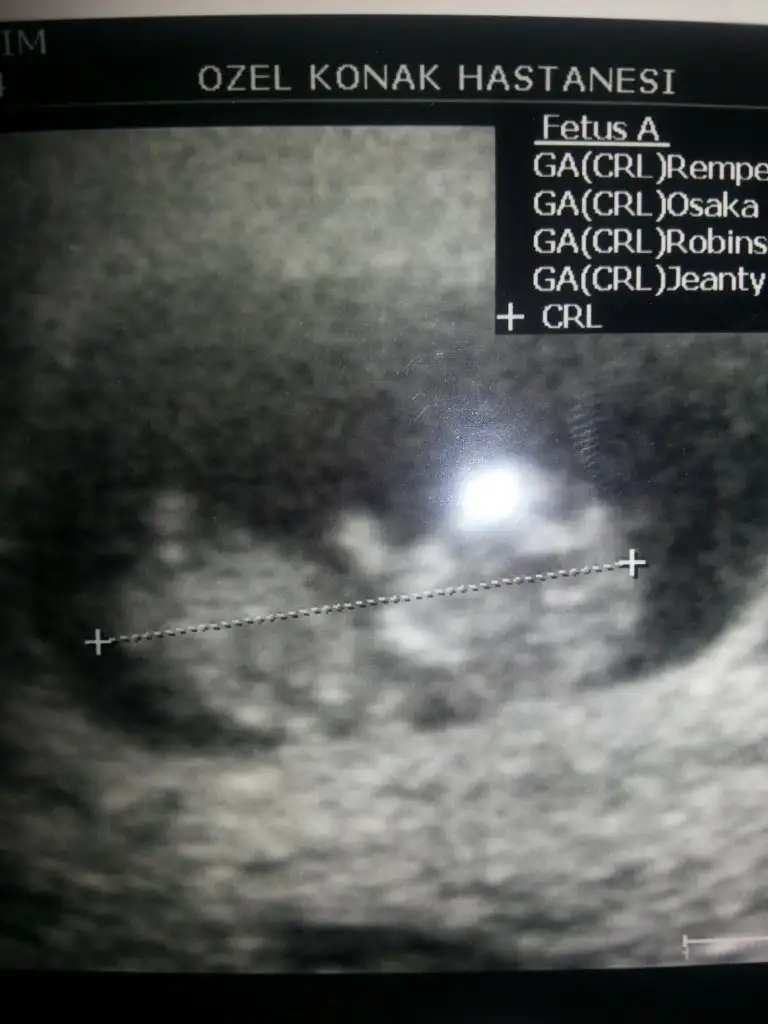

Evveet teyzoşlarıı yorumları alalım bu arada ikiz olduğu için orda iki bebek var ama bende hangisi 1 hangisi 2 bilmiyorum

dr soylemeden siz gorun genital nub teorisi ( bebegin cinsiyeti)